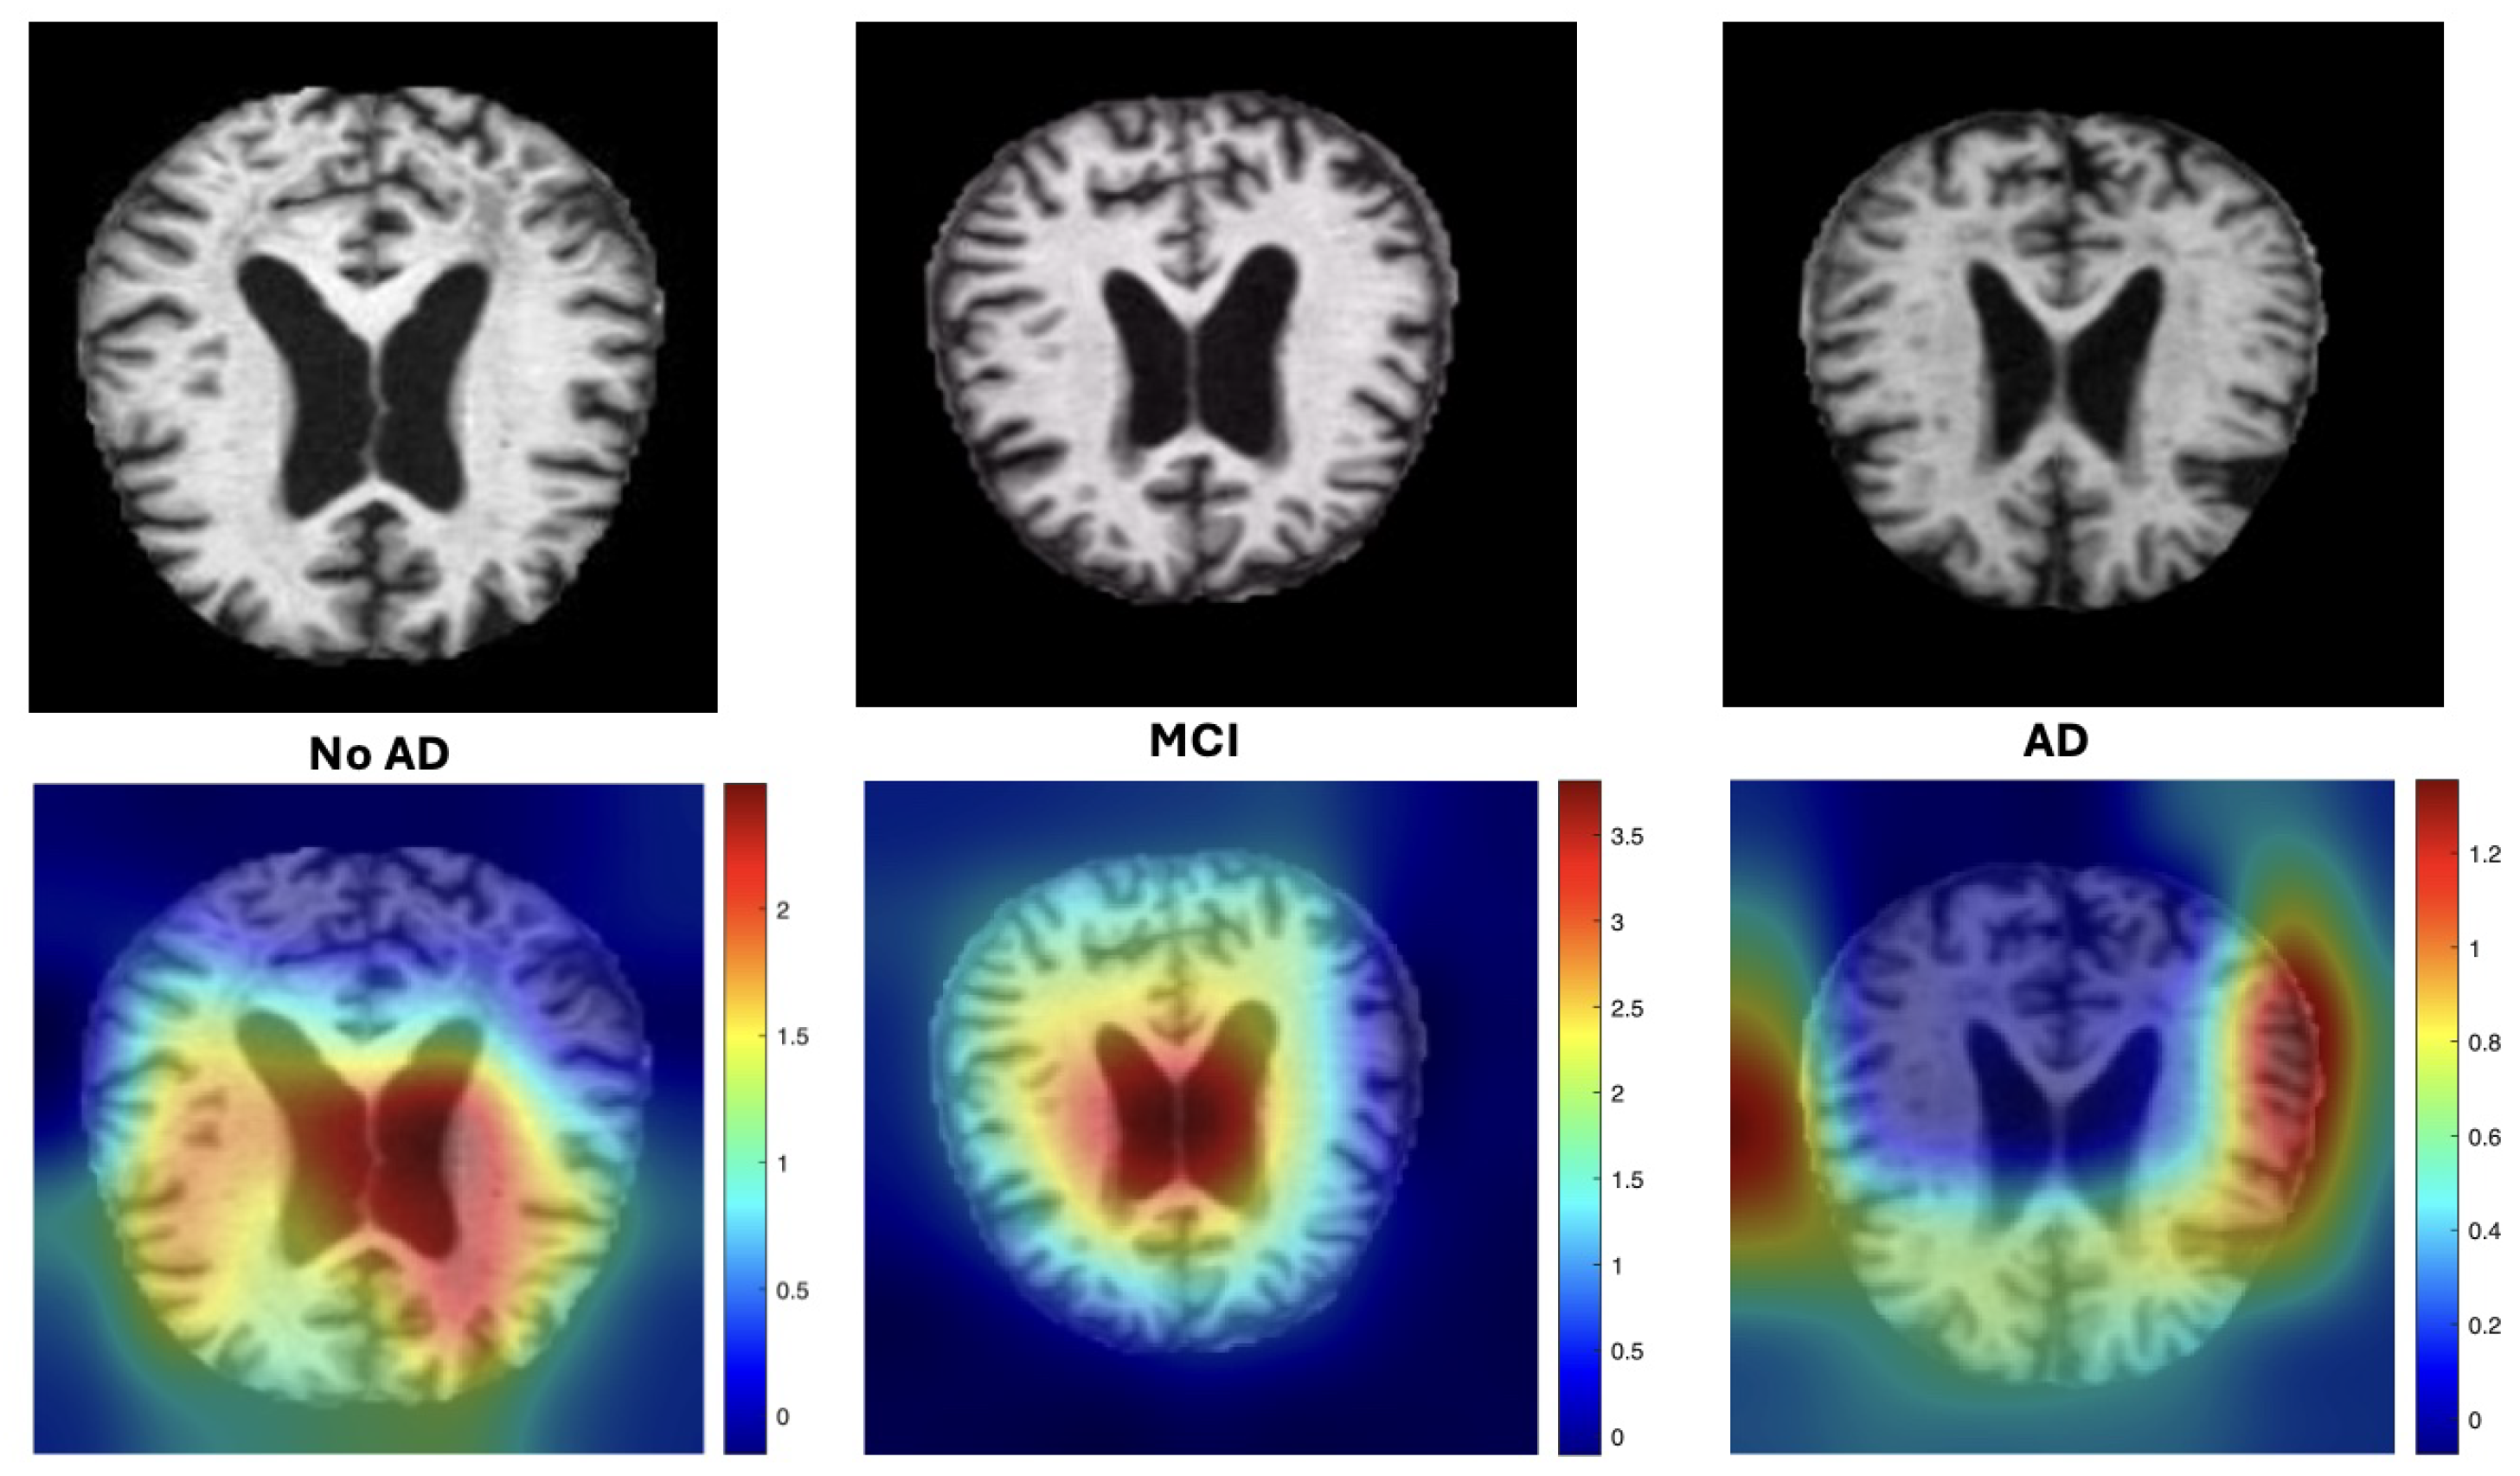

- We incorporate interpretability through Grad-CAM overlays (Figure 1), which demonstrate that the model consistently attends to clinically relevant neuroanatomical regions associated with AD progression.

3.4. Gradient-Weighted Class Activation Mapping

3.6. Gradient-Weighted Class Activation Mapping (Grad-CAM)